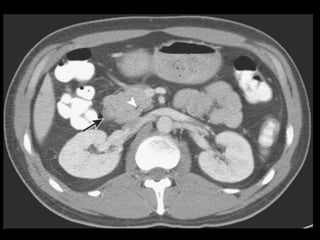

Coleções líquidas agudas

Ocorrem em cerca de 40% dos casos;

Podem ser em torno da glândula ou extra-

pancreático;

Carecem de cápsula e são confinadas ao espaço

anatômico onde se encontram;

Podem dissecar para outros locais: mediastino,

pararrenal posterior, órgãos sólidos ou parede de

alça intestinal.

Coleções líquidas agudas- TC

Hipodensas

Mal definidas

Sem cápsula ou parede reconhecível

Resolução espontânea em 50% dos casos;

Complicações: dor, infecção secundária e

hemorragia;

São passíveis de drenagem percutânea caso não

regridam ou se tornem infectadas.